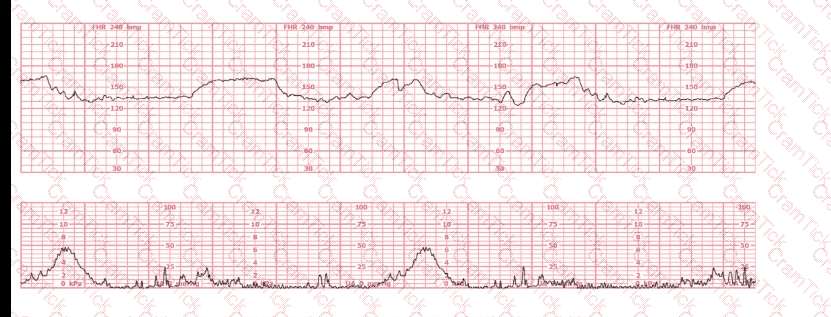

This is a fetal heart rate tracing of a multiparous woman whose cervix is 7 cm dilated on admission. The most likely cause for this pattern is: